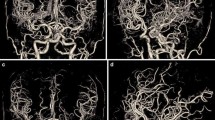

A clear depiction and delineation of small, peripheral vessels in a patient example is given in Fig. 4, and the remarkable superiority of UHR-CT in the visualization of peripheral and small vessel branches and their delineation is demonstrated in volume rendering (Fig. 5). The improved image quality of the vertebrobasilar area is also substantial: VA: UHR-CTA = 4 (4–4) vs NR-CTA = 3 (3–4) PICA: UHR-CTA = 4 (3–4) vs NR-CTA = 3 (2–3); AICA: UHR-CTA = 4 (3–4) vs NR-CTA = 3 (2–3). The apparent differences in delineation of peripheral cerebral vessels are illustrated in Fig. 5.

Example of a UHR-CTA of a female 41-year-old patient. a Volume rendering technique in the sagittal plane. b Maximum intensity projection with a slice thickness of 17.5 mm in sagittal view; c Maximum intensity projection with a slice thickness of 17.5 mm in Towne view for tracing the vascular course of the posterior cerebral artery. The superior image quality and the distinct delineation of the peripheral sub-segments are emphasized

Two exemplary patients with the same clinical characteristics. a Maximum intensity projection with a slice thickness of 17.5 mm calculated on an UHR-CTA data set in sagittal view. b Maximum intensity projection with a slice thickness of 17.5 mm calculated on an NR-CTA data set in sagittal view. In contrast to NR-CTA, the significantly improved visualization of the small vessel branches in UHR-CTA can be considerably emphasized